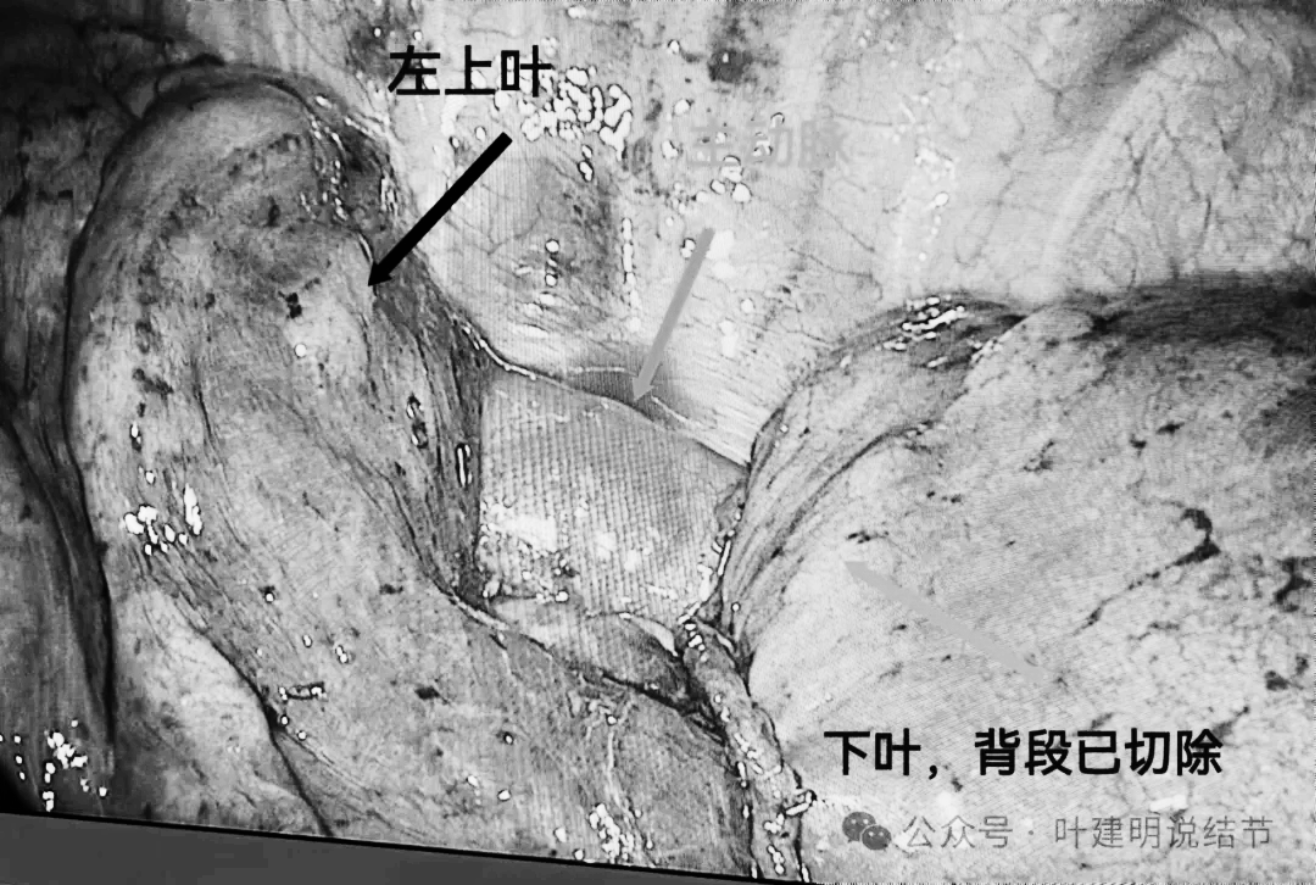

患者入住杭州市第一人民医院胸外科,由叶建明团队安排手术。做了单孔胸腔镜下左下叶背段切除加淋巴结采样。

标本镜下观,CT上紧贴主动脉壁,其实进胸后并没有侵犯到主动脉壁的,肺萎陷后就脱开的。病灶表面胸膜有皱缩,质较硬。

背段切除后胸内的样子。